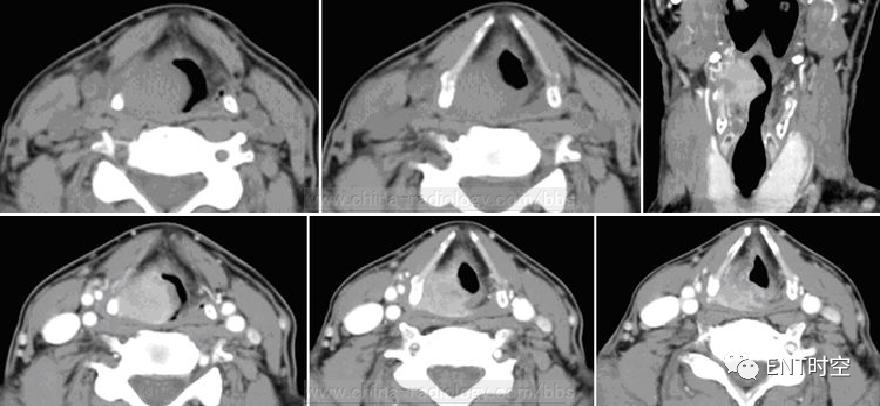

一、咽后壁脓肿

女性,54岁,误食猪骨头3日、加重伴颈部肿痛2天。

(一)影像所见:

平扫示咽喉后间隙及椎前间隙增、可见弥漫性肿胀影,病变区边界欠清,肿胀区内可见多发点状气体影。病变范围累及双侧咽旁软组织。矢状重建示咽后壁明显增厚。

(二)诊断:

咽后壁脓肿手术后确诊患者皮下气肿范围为上至双侧颌下区,下至胸骨下平面,双侧至锁骨中线。全麻成功后支撑喉镜下见白色梭形猪骨横行卡于左侧梨状窝处。

(三)鉴别诊断:

1.下咽癌 2.淋巴瘤

CT诊断:影像检查首选,能够诊断患者是否有脓肿,并可与颈部其他病变相鉴别。同时还能区分不同层面是否有分隔及液体积聚,这些是化脓性感染的特征表现。CT表现为稍低密度,与周围组织界限不清,并有周围软组织的肿胀,部分脓肿腔内可见气体影。

1、与下咽癌的鉴别:

下咽癌显示一侧披裂会厌壁增厚,梨状隐窝呈环状狭窄,甚至闭塞,肿瘤有一定的破骨作用,双侧颈部可见肿大的淋巴结。咽后壁及咽后区肿瘤可表现为咽后间隙增宽,肿瘤范围不如炎症弥散,且没有气体影,结合临床病史不难诊断

2、与淋巴瘤的鉴别:

病变表现为软组织样多发结节密度影,常有身体其他部位的淋巴结肿大